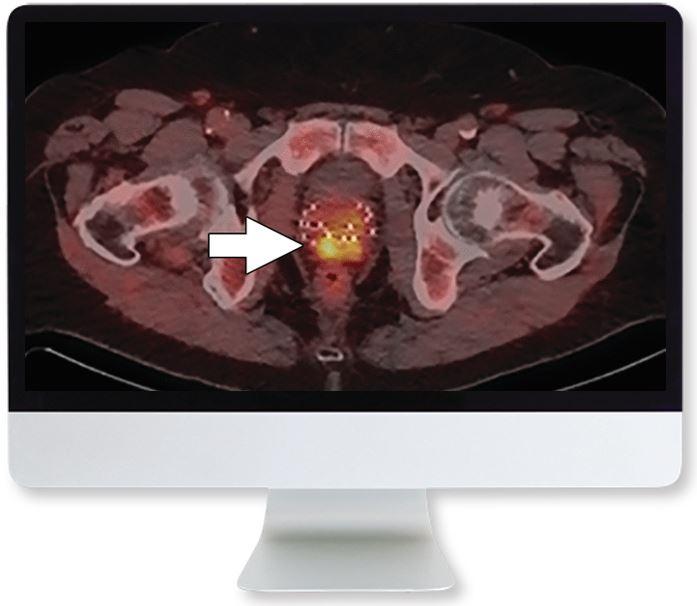

Full Video Course

Experts from the Society of Nuclear Medicine and Molecular Imaging will speak on the most advanced nuclear medicine technology in both the imaging and therapy of prostate cancer. Prostate specific membrane antigen (PSMA) has been extensively studied as both an imaging and therapeutic target for prostate cancer and therefore also as a theranostic target. PSMA-targeted radiopharmaceuticals for PET imaging and for delivery of therapeutic radiation are now in phase 3 trials and thus may soon be available to greatly expand the role of nuclear medicine in the care of patients with prostate cancer.

- describe the capabilities of PSMA-PET imaging for prostate cancer

- discuss PSMA targeted PET interpretation

- PSMA-targeted PET Imaging for Prostate Cancer—K. Zukotynski